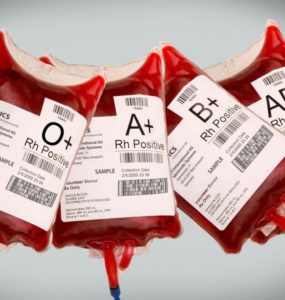

الدم الصناعيّ.. بين التجربة والتطبيق

لقد سمعنا من قبل عن زراعة الكبد والكلى وعن صمام القلب الصناعي وعن دراسات مبدئية عن كلية صناعية، ونسمع كل يوم عن اكتشافات واختراعات كبيرة في المجال الطبي؛ ولكن هل خطر ببالنا أنه سيأتي يوم يتم فيه تصنيع الدم الذي يسري...